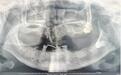

王婆婆口腔影像图

半个多月前,家住武汉的王婆婆感觉口腔内脓肿疼痛。老人自以为是上火了,并未在意。在家拖了一周后,肿痛反而越来越严重,王婆婆这才来到武汉市第四医院口腔科就诊。王婆婆对医生说:“嘴都快张不开了,吃饭很困难。”接诊的口腔科主任向国林详细检查了王婆婆的情况,发现她左侧上颌腭部严重红肿化脓,组织肿胀已经影响到患者进食和呼吸,如果任由情况恶化,会有更多组织感染肿胀,严重时甚至会堵塞气管,导致患者窒息死亡。经过拍片检查,医生发现引起王婆婆严重感染的罪魁祸首竟然是一颗埋伏阻生智齿。

向国林介绍,智齿一般在16岁到25岁萌出,但是部分智齿受邻牙、牙槽骨或软组织的影响,可能无法长出来,成为埋伏阻生智齿。“完全埋伏阻生的智齿在牙龈表面完全看不见,易被误认为没有长智齿,只有通过拍片才能发现。”向国林解释,导致王婆婆口腔感染的就是这样一颗埋伏在牙槽骨中的智齿。等到患者高龄,牙槽骨吸收萎缩、身体免疫力下降,口腔细菌进入牙齿周围就引发了炎症,由于没有及时治疗,患者的感染逐渐加重,引起周围组织肿胀化脓。